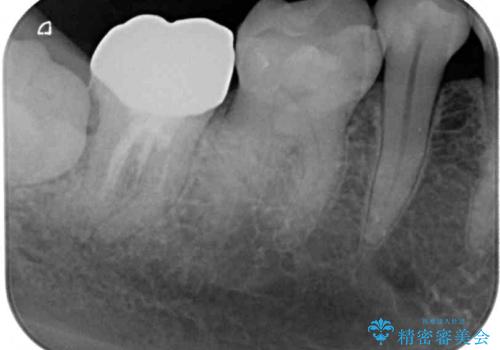

- かかりつけ医にて、歯の高さが不足しているためセラミッククラウンの装着はできないと言われたとのことで来院された患者様です。

診察したところ、確かに歯の高さは不足していましたが、土台の立て直しや歯の削り方を調整することでオールセラミッククラウンでも補綴可能と思われました。

ただし、クラウンの厚みは極力薄くした方が維持力が増すため、高強度のフルジルコニアクラウンにて補綴治療することとしました。